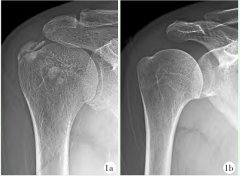

临床医师只有深刻掌握RCCT的流行病学、病理过程、辅助检查等基本知识,才能正确选择治疗方式及其手术治疗时机。本文报告1例手术治疗RCCT患者...[全文]

添加时间:2023-01-31关键词: 肩袖钙化 肌腱炎 诊疗误区